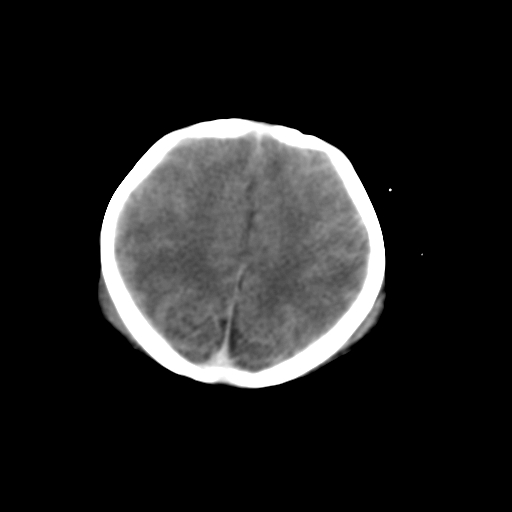

新生儿女2天,有窒息史,经抢救好转!白质最低ct值>23hu,请教各位老师:是否有出血?是否合并缺氧脑病?谢谢!

hie、蛛网膜下腔出血,皮下血舯。

双侧额叶白质低,白质ct值低于18hu可以考虑水肿改变

后纵裂密度高,前纵裂密度低,比较来说应该考虑有蛛网膜下腔出血

空三角征,蛛网膜下腔出血。